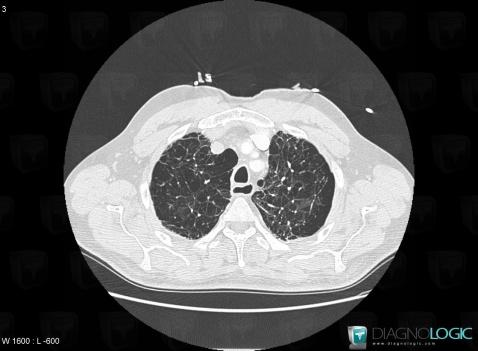

COPD, Pulmonary parenchyma, CT

Here is the specific information in the key image above:

- Diagnosis COPD, Location(s) Pulmonary parenchyma, with gamuts